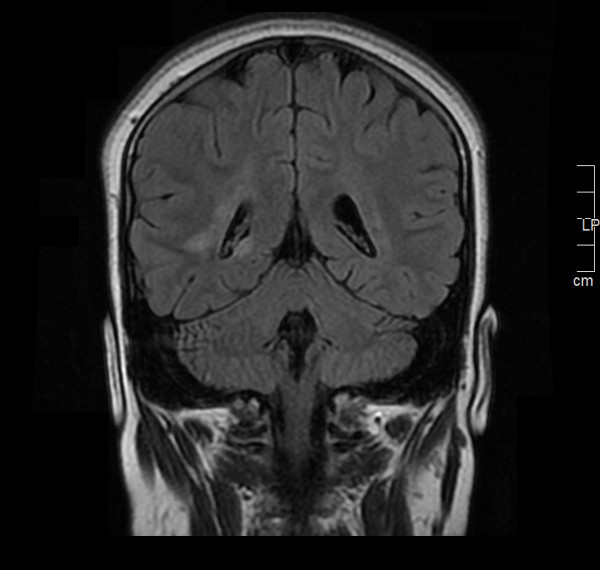

Cinco meses después del inicio de la clínica se solicita de manera ambulatoria una nueva resonancia craneomedular.

En comparación con el estudio previo, han aparecido nuevas lesiones a nivel infratentorial, tanto en el bulbo como en la protuberancia y el mesencéfalo.

La disposición de las lesiones es muy sugestiva de enfermedad desmielinizante y se cumplen criterios de diseminación en espacio y tiempo de esclerosis múltiple con signos de actividad y progresión.